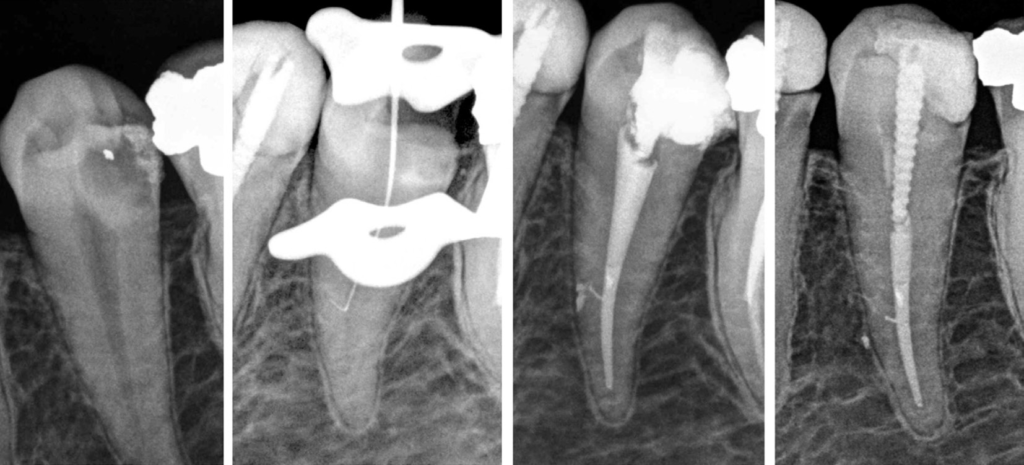

This is a series of 7 cases in which the operator penetrated lateral canals with instruments. Two teeth presented with irreversible pulpitis, 4 with necrotic pulps, and 1 with previous treatment. Except for the teeth with pulpitis, all the others were associated with apical periodontitis. The main root canal was always relatively straight, with the lateral canals at the middle third of the root. Suggestive images of lateral canal presence were seen on periapical radiographs in five cases. The clinician introduced intentionally small hand instruments in the lateral canal in 5 cases, while the penetration was fortuitous in the others. The lateral canals were filled in all cases. Follow-up examination was possible in five cases, all of them showed evidence of successful clinical and radiographic outcomes. Introducing files into lateral canals may permit some preparation and penetration of irrigant solution, favoring disinfection and, consequently, enhancing the treatment outcome.